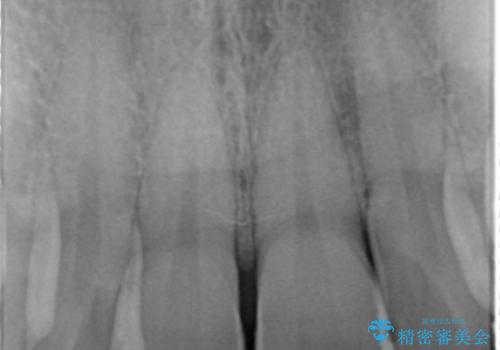

- 左の前歯が黒いとのことで来院。

1番目の歯は小さい虫歯があったのでプラスチックの樹脂で治療をしました(保険内)。

2番目の歯は二箇所虫歯があり、プラスチックの樹脂で治療するとつぎはぎみたいになってしまうので、

白い被せ物(ジルコニアクラウン)で治療しました。